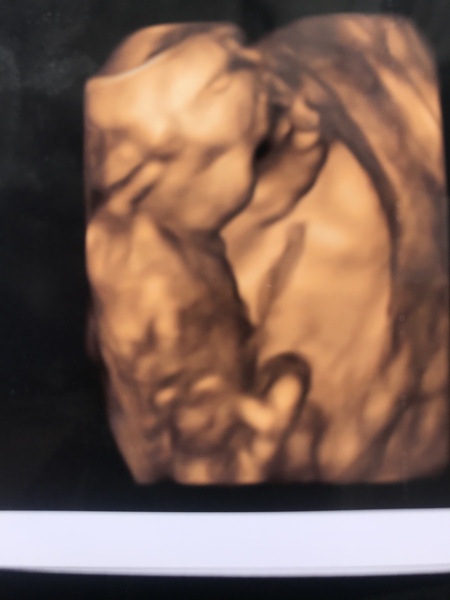

InOmniaParatus13 · 24/08/2019 13:23

I’M HAVING A BOY!!! 💙

He is absolutely perfect and has the most gorgeous long legs!

I’m measuring 16+1 so due date is 7th Feb!

I’m so in love! Here’s my son 😁